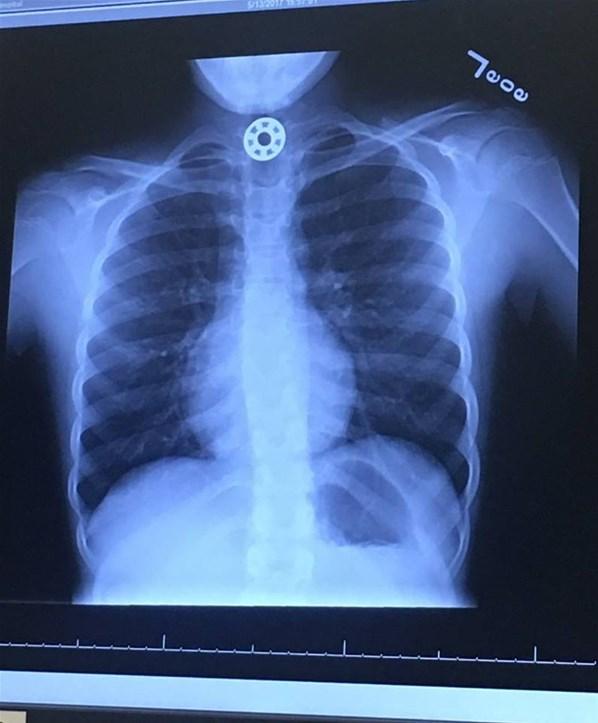

Houston'ın hemen kuzeyinde, The Woodlands'daki Teksas Çocuk Hastanesine götürülen çocuğun yutağında bilye büyüklüğünde bir şeyin sıkıştığı görüldü ve hemen ameliyat yapılması gerektiği söylendi.